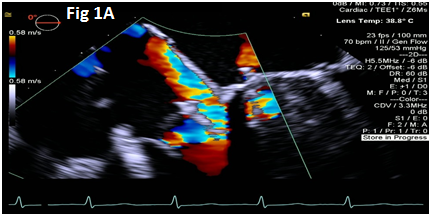

A 73-year-old female with mechanical mitral valve, tricuspid annuloplasty (32mm Edwards Physio Tricuspid incomplete ring) underwent Transcatheter Tricuspid Valve Replacement (TTVR) using off-label 29mm Edwards Sapien 3 (S3) Transcatheter Heart Valve (THV). Immediate post valve deployment, mild Perivalvular Leak (PVL) was noticed at the septal aspect (area of incomplete annuloplasty ring). Eighteen months later, patient presented with recurrent right heart failure and paracentesis due to severe tricuspid PVL (Figure 1A-C, Video 1). Percutaneous PVL closure under general anesthesia, Trans-esophageal Echocardiography (TEE) was performed. Via femoral venous access, defect was easily crossed with Agilis steerable sheath, multipurpose catheter and 0.035” glide wire. Despite recurrent attempts, wire came through the PVL but then traversed through open cells of S3 into the right ventricle (Figure 2A), confirmed with Armada 6mm balloon waist at the S3 cage (Figure 2B) (despite inflating 28mm Z med balloon inside S3 cage, Figure 2C). We decided to partially deploy the plug and assess valve function. Using 7.5F Asahi Eaucath multipurpose guide, a 12mm AmplatzerTM Vascular plug II (AVP II) was advanced through the defect. The ventricular disc was opened inside the S3 cage while body in the PVL defect (outside the S3 cage) and atrial disc on the atrial side of PVL (Figure 3A-B). With S3 function unaffected, no central leak and minimal gradient, PVL reduced to mild severity (Figure 4A-D, Video 2); the AVP II was successfully deployed (Figure 5). At 3-month follow up, there was an excellent symptomatic improvement (NYHA functional class I), with no heart failure re-hospitalization or paracentesis. Deployment of plug disc inside the valve frame is not recommended due to fear of interference with leaflet function and possible injury in long term. There was no immediate issue with the valve function in this case (due to space between the leaflet and frame of S3 and depends on size of plug used). Valve-in-Valve (S3-in-S3) would have certainly sealed all open cells treating this PVL but is more expensive option.

Figure 2 Multi-purpose diagnostic catheter (MPA) crossing through the PVL proximally and through the S3 cells distally (A), balloon inflation over a wire passed through the PVL channel confirms the position of hour-glass shaped inflated balloon with proximal half outside & distal half inside the S3 cage and waist in the middle (B), along with failed attempt to cross the MPA (white arrow in C) with Safari wire along with Zmed balloon inside the S3 (black arrow).